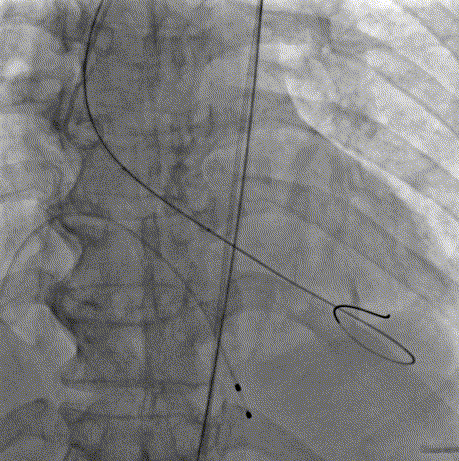

术前主动脉根部造影

20mm球囊预扩

AV26瓣膜定位

AV26瓣膜工作位造影

AV26瓣膜释放

术后主动脉根部造影

本例手术为重度钙化二叶式病变重度主动脉瓣狭窄TAVR手术,团块状钙化挤压存在移位瓣周漏风险,术前手术团队对患者进行了全面细致的评估,确定假体瓣膜锚定区域范围,制定术前释放策略。何柳平主任团队通力配合、精准释放,充分利用TaurusElite可回收功能,在瓣膜释放至2/3时,多角度评估瓣膜植入深度、锚定力以及冠脉灌注情况,确认瓣膜植入深度合适、锚定力稳定,缓慢逐个脱钩,进行瓣膜释放。释放后造影显示瓣膜膨胀良好,行血流动力学评估,跨瓣压差从术前100mmHg降至15mmHg,少量瓣周漏,手术圆满完成。